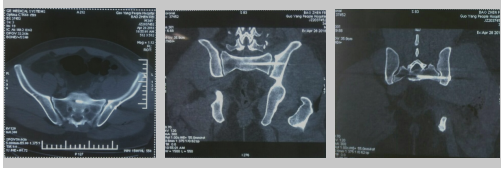

图:U、V、W、X、Y、Z术后CT

以下图片是我科骨盆髋臼骨折腹直肌外侧入路手术技术的两例患者资料。(骨二科)

实例一

实例二